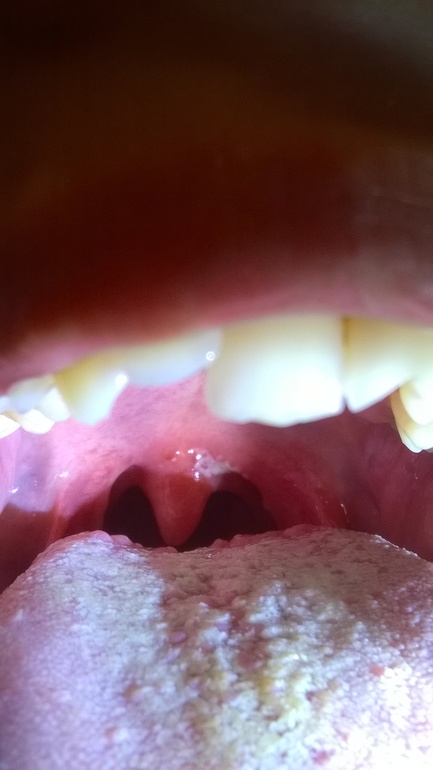

Налет на горле

Стоматит кандидозный, например. К Лору загляните.

спасибо. похоже на него.... обязательно схожу